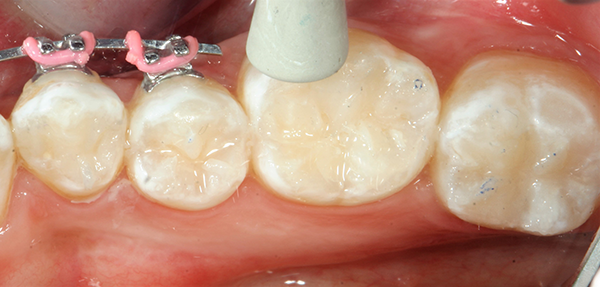

After local anesthetic was administered, all visible decay was removed (Fig. 1) and, following the latest Dental Caries 2018: New Insights recommendation, all “affected” dentin layers were also removed. The preparation was disinfected with 5 percent gluteraldehyde-35 percent hydroxylethyl methacrylate (HEMA) formulations applied with Ball-Point Applicators™by KaVo Kerr.

Fig. 1 Fig. 2

After the two separate one-minute applications of disinfectant, the restorations were suctioned to achieve a damp surface.2 This step was followed by the application of OptiBond™ All-In-One self-etching dental adhesive by KaVo Kerr with Ball-Point Applicators (Fig 2 ).